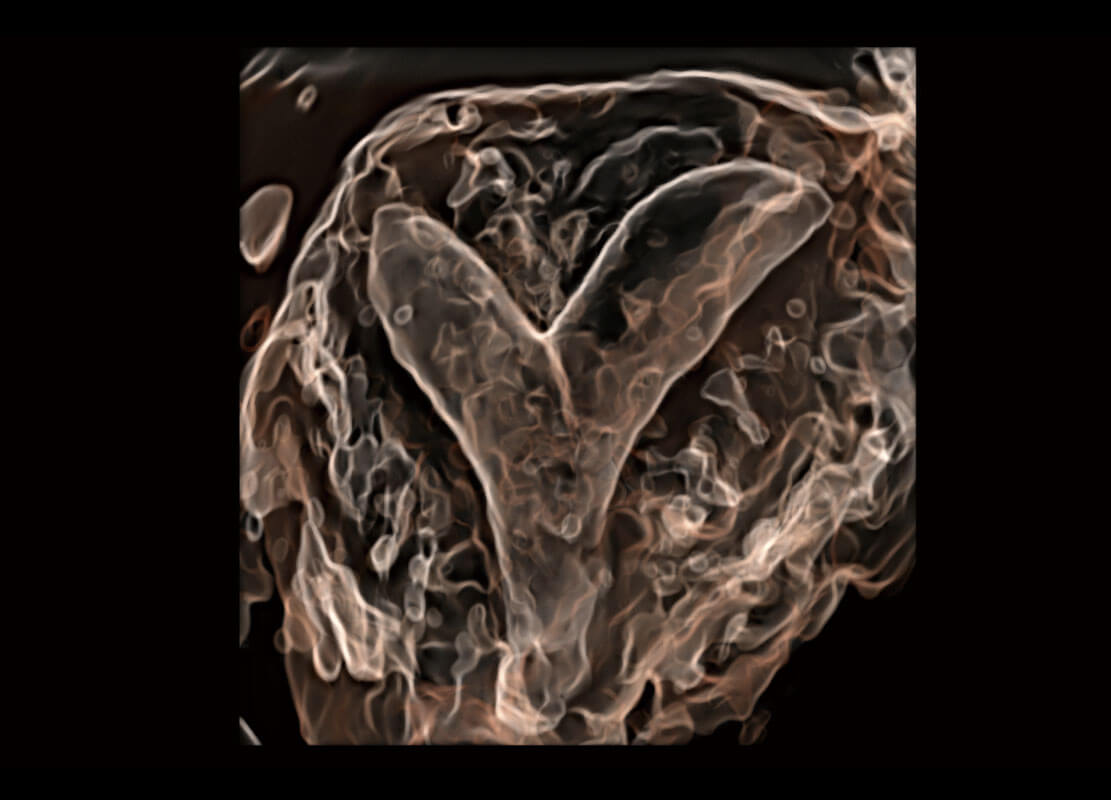

P60搭载一系列胎儿心脏成像技术,实现精细的胎儿心脏评估。

四腔切面

右室双出口

胎心容积成像